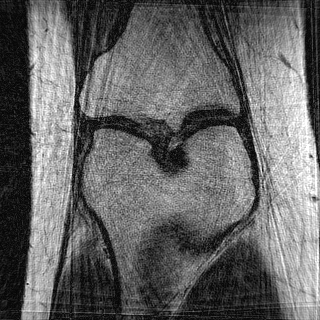

This article presents a novel undersampled magnetic resonance imaging (MRI) technique that leverages the concept of Neural Radiance Field (NeRF). With radial undersampling, the corresponding imaging problem can be reformulated into an image modeling task from sparse-view rendered data; therefore, a high dimensional MR image is obtainable from undersampled $k$-space data by taking advantage of implicit neural representation. A multi-layer perceptron, which is designed to output an image intensity from a spatial coordinate, learns the MR physics-driven rendering relation between given measurement data and desired image. Effective undersampling strategies for high-quality neural representation are investigated. The proposed method serves two benefits: (i) The learning is based fully on single undersampled $k$-space data, not a bunch of measured data and target image sets. It can be used potentially for diagnostic MR imaging, such as fetal MRI, where data acquisition is relatively rare or limited against diversity of clinical images while undersampled reconstruction is highly demanded. (ii) A reconstructed MR image is a scan-specific representation highly adaptive to the given $k$-space measurement. Numerous experiments validate the feasibility and capability of the proposed approach.